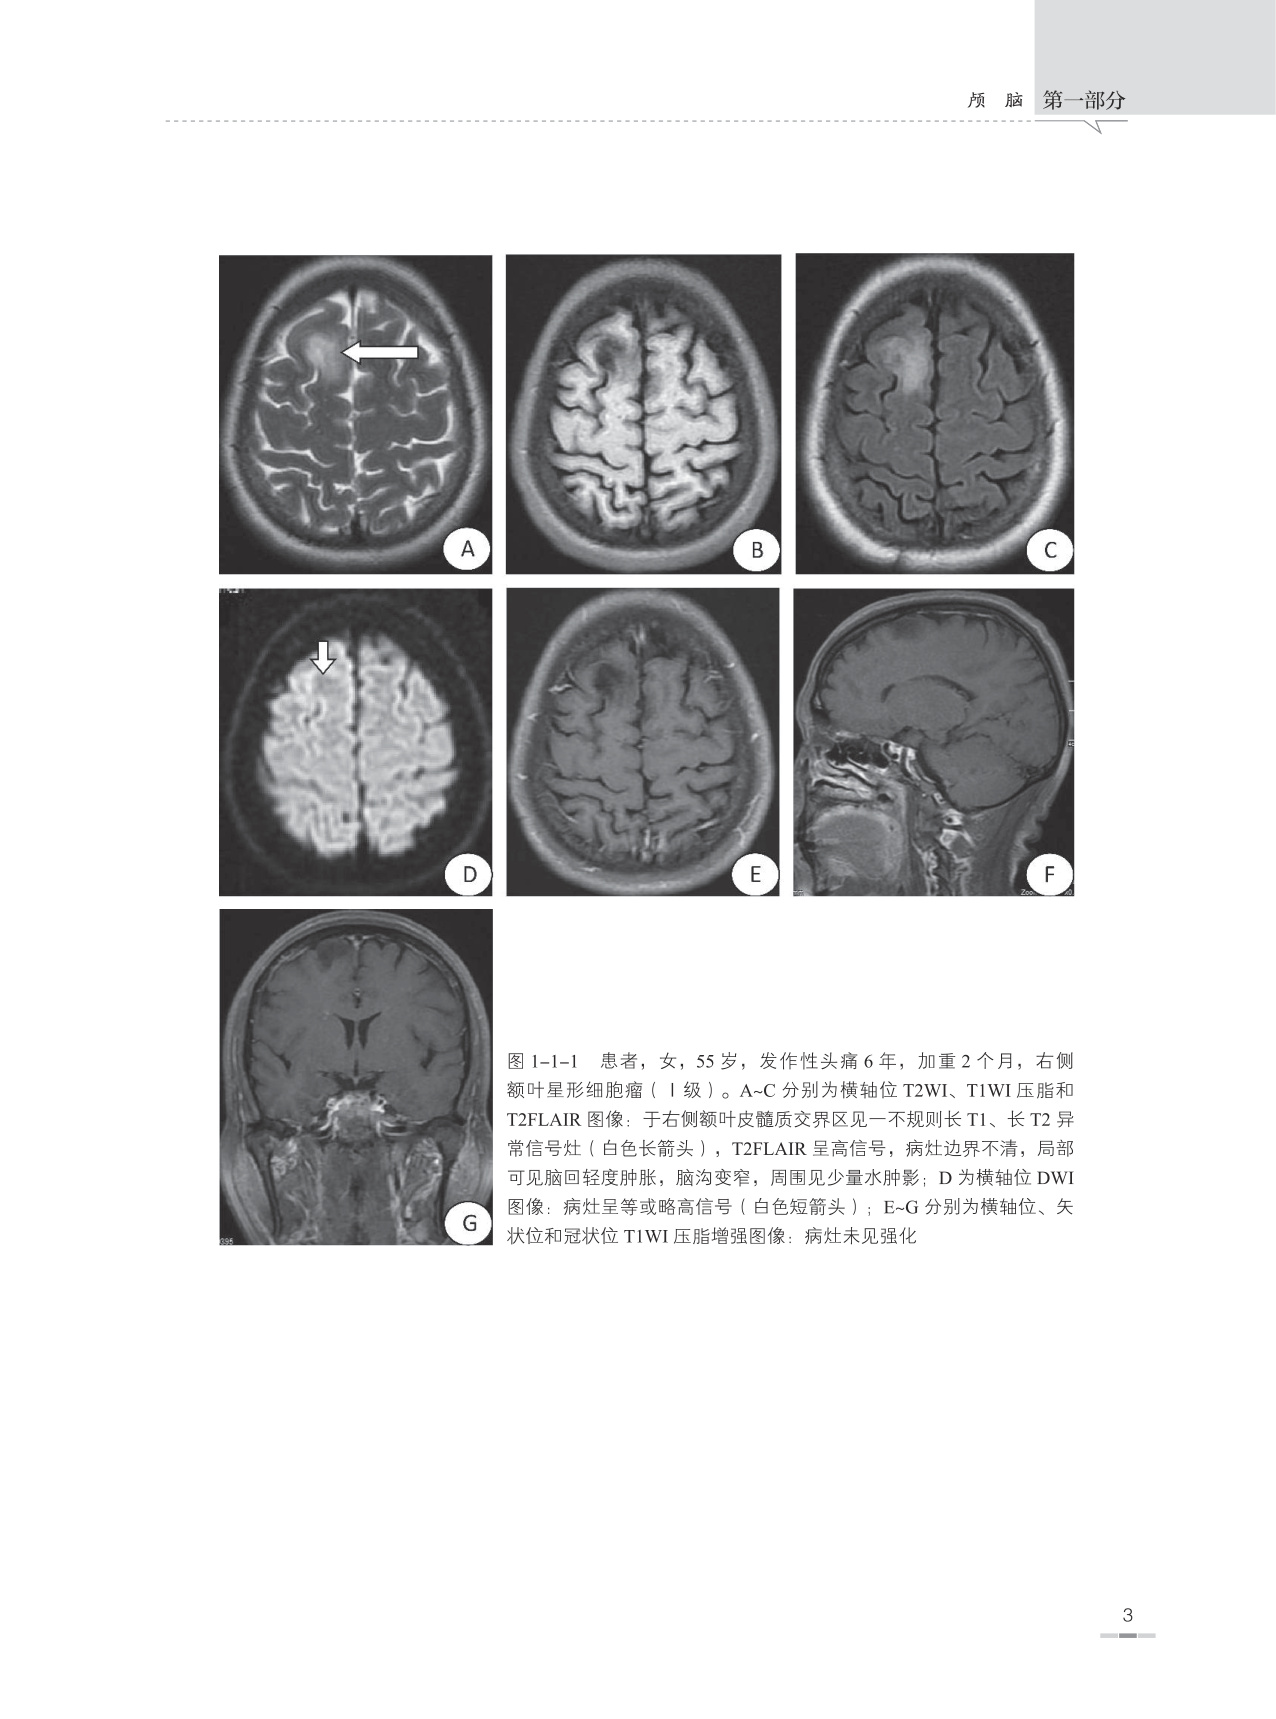

本书是根据作者本人多年临床工作经验并参考大量中外文献资料编写而成的,书内附图均为作者在40余年日常临床医学影像诊断工作中所收集留存的典型病例,书中对每一种疾病所涉及的内容包括疾病概述、流行病学、治疗与预后、病因、发病机制、病理、临床表现、影像学表现、典型病例图像、鉴别诊断及主要参考文献,以便读者能够全面理解和掌握疾病的临床及影像学表现特征。另外在每一种疾病论述开始之前附有本疾病的主要表现特征和诊断要点,以便读者能够快速掌握疾病的重点。

本书主要面向医学影像学诊断医师和医学影像学专业学生,并力求为各级医院神经内科、神经外科、急诊科、ICU、肿瘤科、脊柱外科、康复科、介入科、放疗科、病理科等相关科室以及全科医师提供神经系统疾病的影像学诊断信息,让广大的临床医师更好地了解医学影像学诊断技能在中